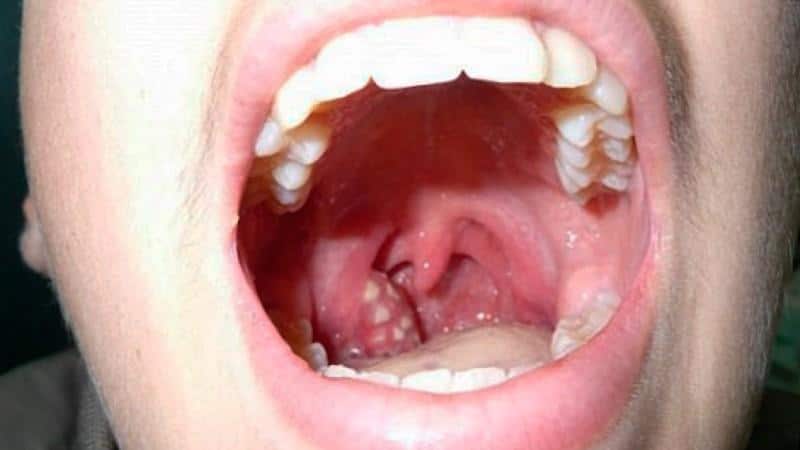

При воспалении небных миндалин пациент испытывает множество неприятных симптомов. К основным из них можно отнести:

- болезненные ощущения при глотании пищи и жидкости;

- покраснение слизистой оболочки;

- изменение цвета миндалин;

- ощущение першения;

- боль в горле;

- налет на миндалинах;

- гнойные выделения;

- белые комочки;

Однако ключевым признаком хронического тонзиллита является отечность небных миндалин и выраженное воспаление в горле. Отек может быть настолько значительным, что приведет к затруднению дыхания.